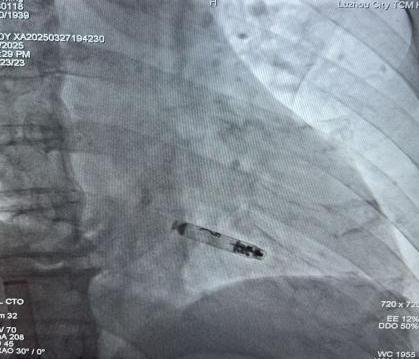

起搏器释放后影像

刘大爷的手术在朱彬带领下实施,在局麻下进行。通过股静脉将约二分之一7号电池大小的无导线起搏器送入他的右心室,再利用独有的螺旋锚定装置牢牢地将其固定于心肌。术中、术后参数测试均良好,如今患者术后恢复良好,心脏逐渐恢复“活力”,未再出现过头晕症状,术后随访提示预估寿命20-30年。